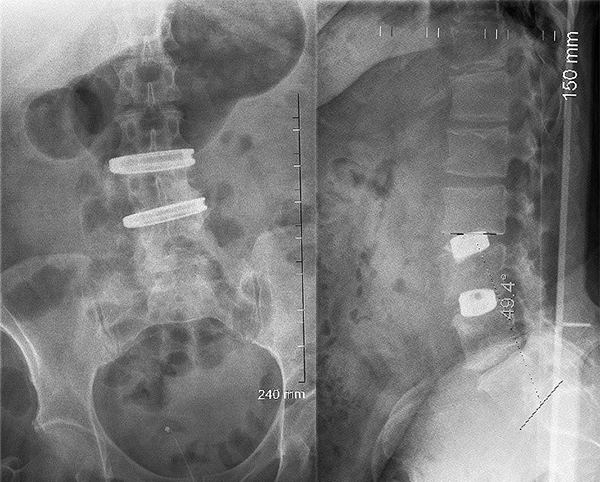

術前

first stageは3日前にLLIF cage (K2M社製のCASCADIA lateral interbody system)をL2/3, 3/4に挿入されており、今回はL4/5に多孔性のチタン製のBOX型TLIF cage (K2M社製のCASCADIA AN interbody system)を後方から挿入し、O-arm navigationでPPS (EVEREST MIS system)をL2からS1まで刺入してカンチレバーテクニックでlumbar lordosisを作るというものでした。ポイントは固定範囲のすべてのfacetに対してfacet fusionを行う点です。PPSにつくプラスチック製のしなやかな2枚羽がretractor代わりになり専用のデバイスを装着するとfacetを十分展開することができ、ここに骨誘導を図る目的でInductigraftという人工骨を置いていました。先生にお聞きすると前方がfusionしてもfacetがfusionされていなければ腰痛の原因になりうるとのことでした。一昨年留学していた時はFacet WedgeというDePuySynthes社製のfacet fusion用のcageを使用されていました。

First stage 終了時

Second stage 終了時